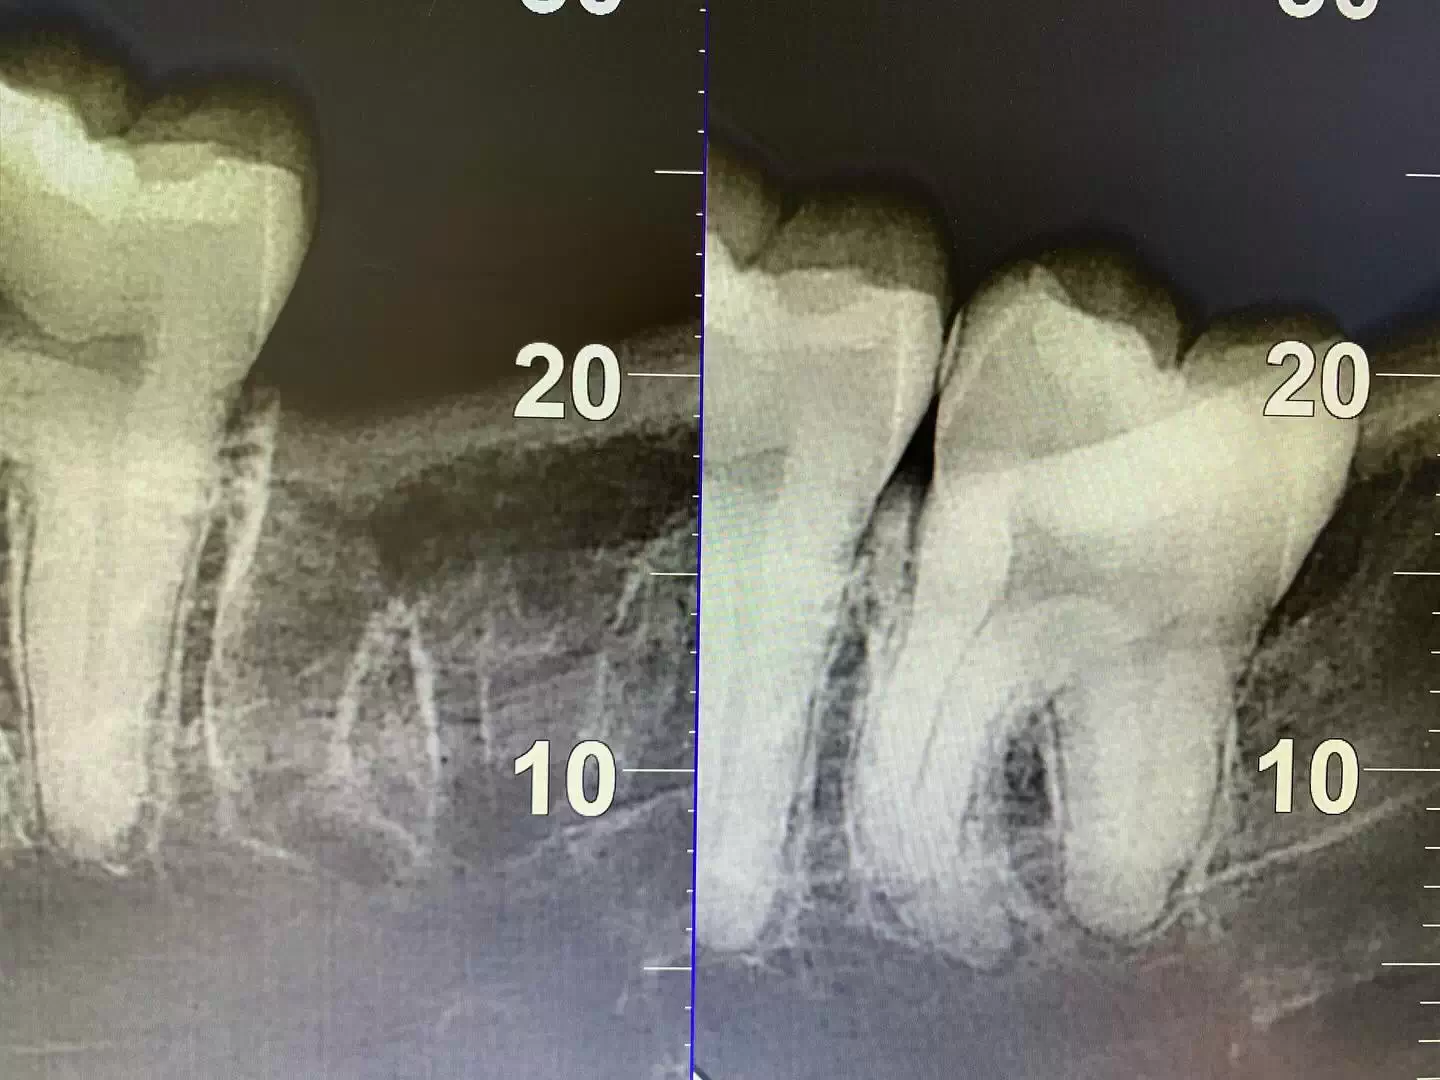

• При гингивите и пародонтите — способствует заживлению десны и восстановлению тканей пародонта.